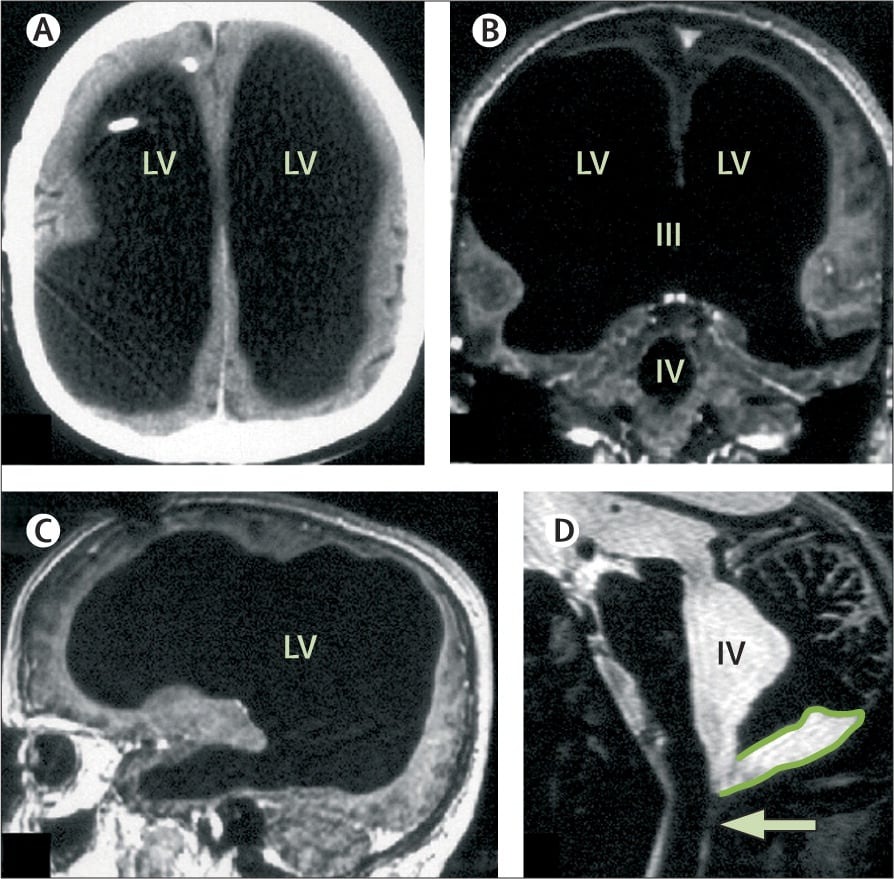

First documented in the medical journal The Lancet in 2007, the case involved a middle-aged man whose brain scans revealed something extraordinary—most of his skull appeared to be filled with fluid, leaving only a thin layer of brain tissue.

He only sought medical help after experiencing mild weakness in his leg. What doctors found during imaging was unexpected: his brain had been severely compressed over decades.

The condition behind this was hydrocephalus—a disorder in which fluid accumulates in the brain. He had been diagnosed as an infant and treated, but after the removal of a shunt in his teenage years, the fluid gradually built up again.

Early interpretations of the case suggested that up to 90% of his brain was “missing.” Later clarification showed that the brain tissue was still present—but squeezed into a thin outer layer.